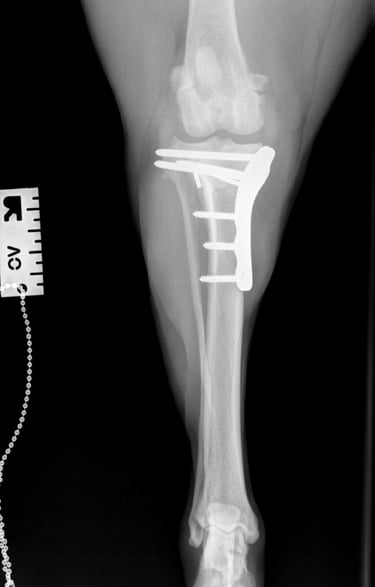

Postoperative radiographs showed that the proximal screw of the distal fragment is slightly longer than expected, but this is not anticipated to cause clinical issues. GImplants are in good position, there is correct compression and alignment is also optimal.

Postoperative TPA measured at 4.3°.

At the first postoperative recheck (day 3), Luna was nearly fully weight-bearing with only mild lameness. The surgical site showed excellent healing and 6 weeks post-op xrays (Figs. 7 and 8) show good ossification of osteotomy line and good position of implants.

Fig. 7

Fig. 8